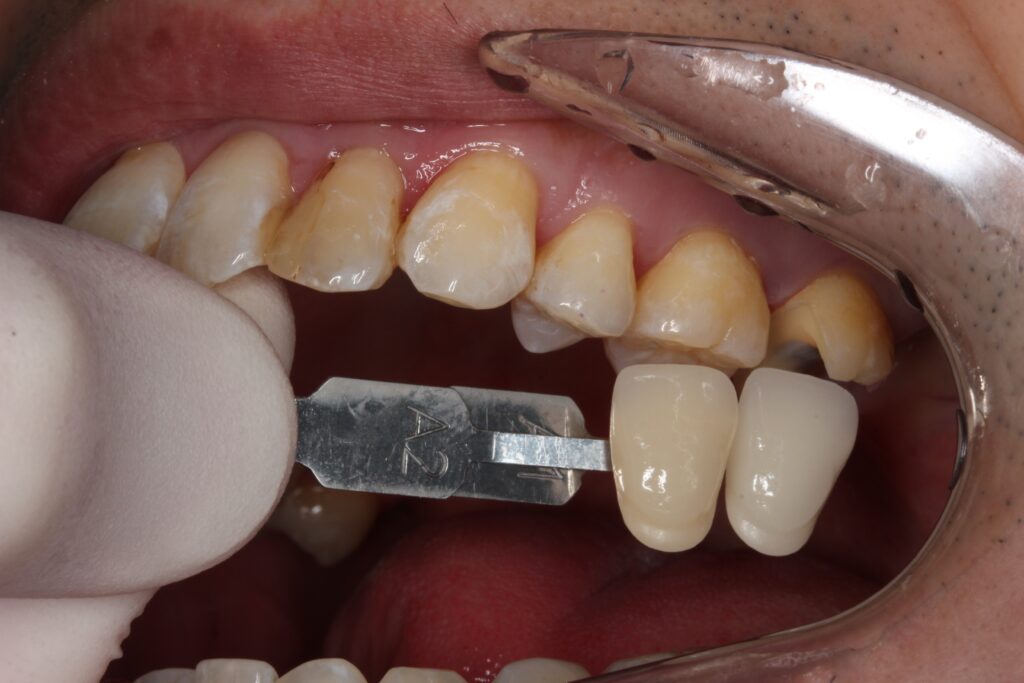

色を合わせ、セラミックインレーを作製します。

治療が終わったお口の中

セラミックをセットして、治療が終わった状態です。

綺麗に仕上がりましたね(^^)/